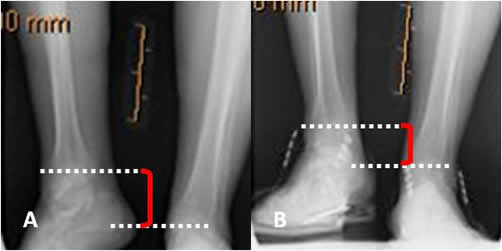

Fig 107. Tratamiento.

Rx AP con plantilla. Acortamiento izquierdo, que disminuye utilizando una plantilla,

aunque persiste elevación de la cabeza femoral derecha y el desbalance pélvico.

Fig 108. Uso de alzas.

A: Telemétrica sin alza y B: Telemétrica con alza. Paciente con luxación abandonada de la cadera derecha (No mostrada) y acortamiento secundario de la extremidad. El uso de la alza en B, disminuye la diferencia de 5 cm a 3.5.